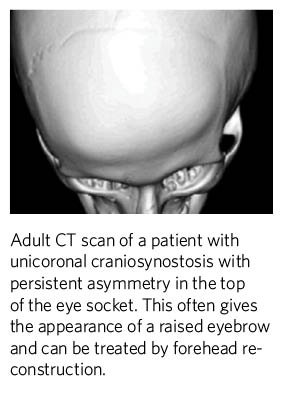

Craniosynostosis

- Patients born with craniosynostosis often undergo surgery on the skull during infancy and throughout adolescence.

- Patients go on to develop asymmetry of the eyes that is often treatable by forehead reconstruction.

- Characteristic deformities of the sides of the forehead are also treatable by cranioplasty, fat grafting and forehead reconstruction.

- Defects of the skull can be treated by cranioplasty and poor scarring can be treated by scalp reconstruction.

- Patients with complex forms of craniosynostosis, such as Crouzon, Pfeiffer or Apert syndrome, often benefit from the above procedures which can also correct prominent eyes (exorbitism).